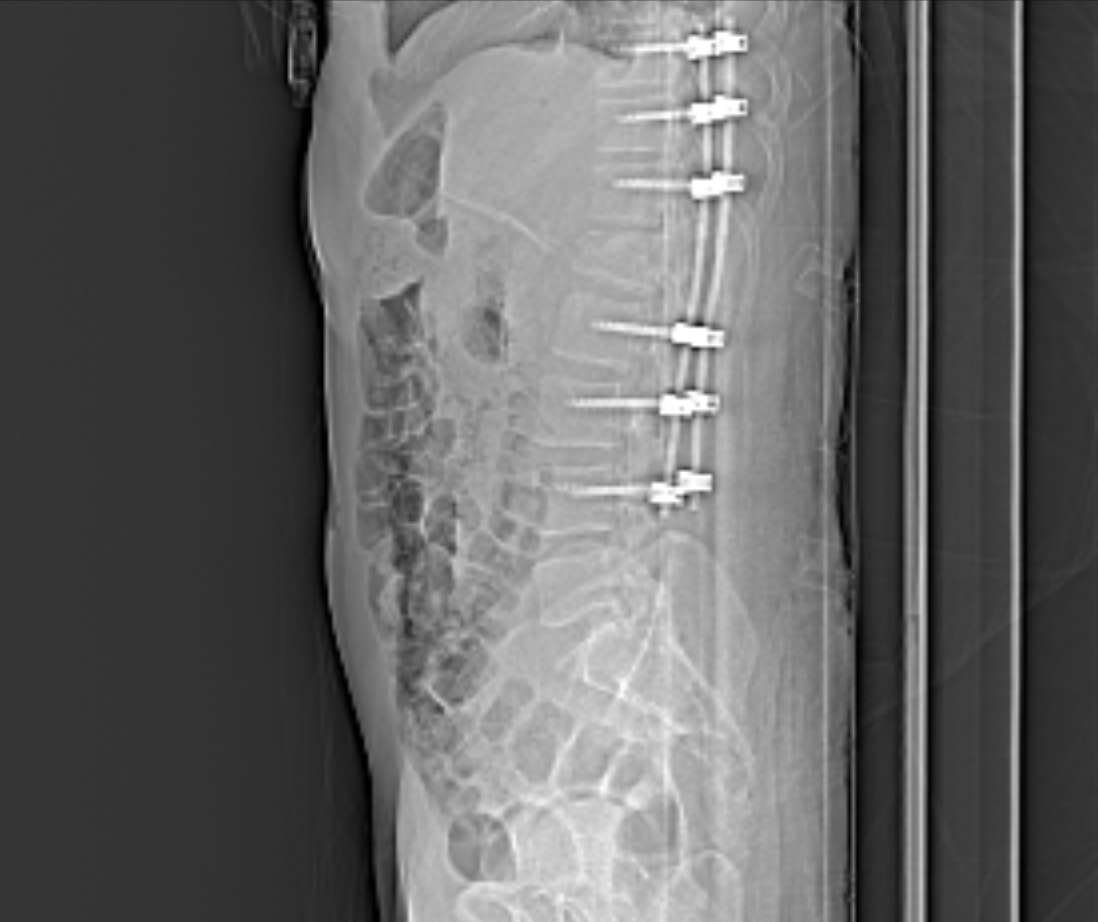

A few months ago I found out how strong gravity is. I had a paragliding accident that has completely changed my life. I ended up with a full spinal cord transection, which means I’m now paralysed from the waist down. It’s been a wild ride since , 4 months in hospital, rehab, and a whole lot of learning how to adapt to a totally new way of living from a wheelchair.